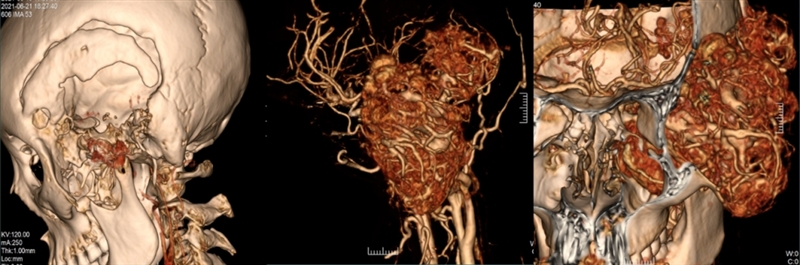

为了尽快给出治疗方案,神经外科主任谢宗义教授立即组织科室进行大讨论。肿瘤巨大,累及重要的解剖结构,而且血供丰富,瘤体内大血管穿行,这意味着手术可能出血多。但对于神经外科擅长血管治疗专业组而言,他们也有应对方法,可以在术前先行造影,明确肿瘤的供血动脉,在情况允许下予以介入栓塞,减少术中出血,然后再切除颅内外肿瘤。

万事俱备只欠东风。6月23日,神经外科在介入室对小辉进行了全脑血管造影,明确肿瘤供血动脉,并尽可能栓塞了颈外的供血动脉,为第二天顺利手术奠定基础。